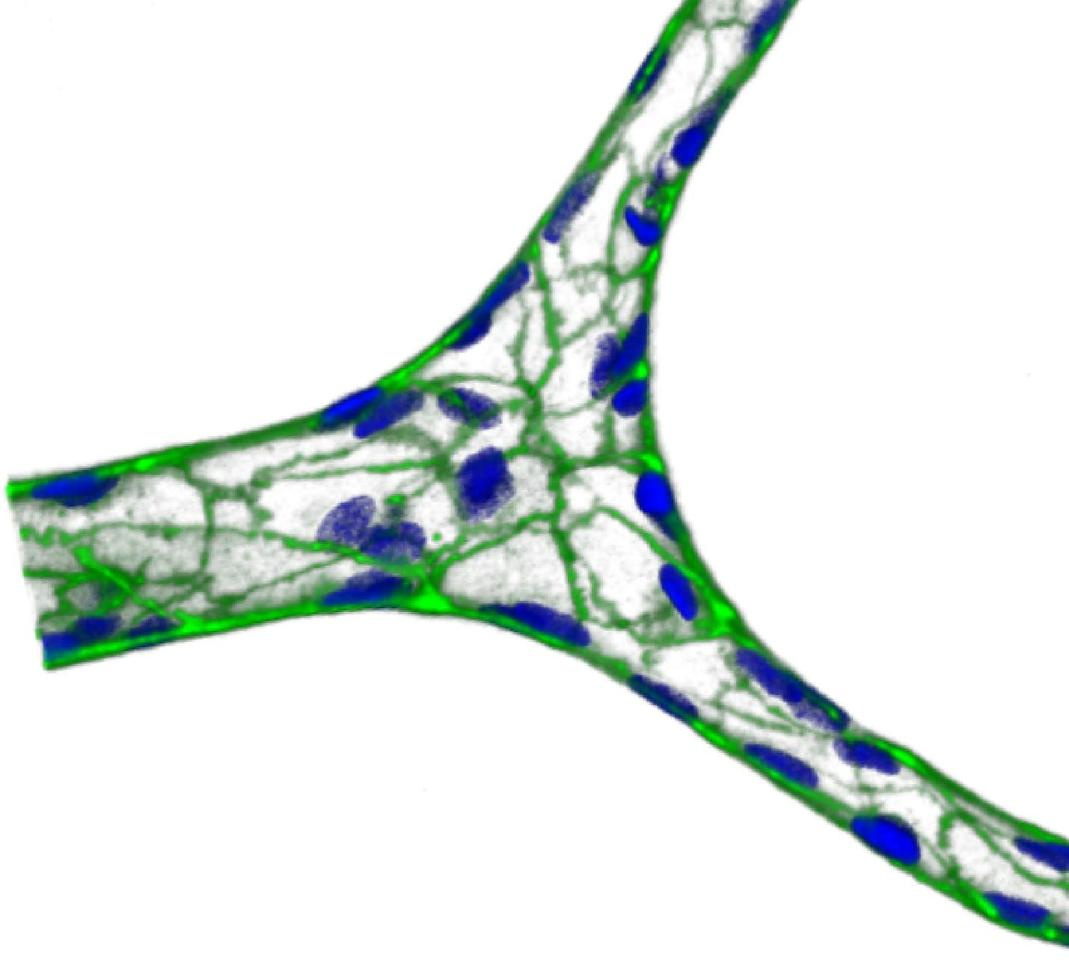

When I joined Wilbur Lam, MD, PhD’s lab in 2012, they had just published a seminal description of their microvasculature-on-chip technology via an “endothelialized” PDMS-based microfluidic approach in the Journal of Clinical Investigation1. Because of my background on biomaterials and vascular tissue engineering, I was challenged by Dr. Lam to develop a microvasculature-on-a-chip 2.0, in which he wanted to replace the PDMS with a more physiologically-relevant biomaterial while also maintaining the branching geometry and size-scale of the vascular space (<30 μm). Moreover, the system had to be perfusable and enable the study of pathophysiological cellular interactions that occur in blood diseases, given that Dr. Lam is a clinical pediatric hematologist as well as a biomedical engineer.

We soon proved that this IPN hydrogel was exactly what we were looking for. After we tuned the IPN to the physiologically-relevant stiffness of the sub-endothelium, we discovered that endothelial cells cultured in the microdevice self-formed a tubular monolayer, self-deposited the appropriate basement membrane matrix, appropriately developed a pro-inflammatory phenotype in response to the cytokine TNF-α and, importantly, exhibited physiological barrier function for well over a month, a feature never reported before for other endothelialized microfluidic devices.

We were very excited about this achievement, as these properties ensure the investigation of the long-term effects on endothelial barrier function that occur in vivo and that are difficult to study using other models, in vitro or in vivo. The first disease we studied was sickle-cell disease (SCD), in which a genetic mutation alters the shape and mechanical properties of red blood cells (RBCs) leading to hemolysis and release of heme in circulation. This platform enabled us to explore how heme and sickle RBC interactions with endothelial cells in and of themselves can induce endothelial barrier dysfunction and microvascular occlusion in SCD, and what the role of the mechanical alteration of RBCs is in this context—an unsolved question in the SCD field (Figure 1).